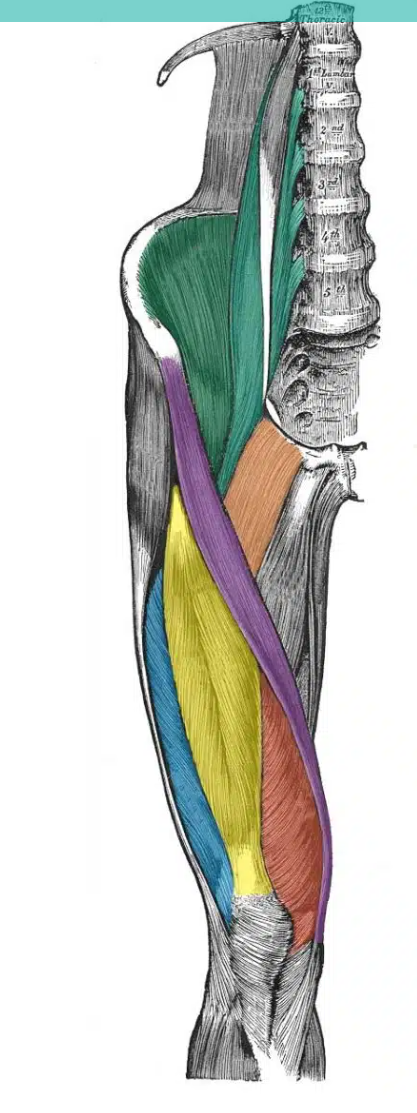

green vertical muscle- close to spine

A

psoas major

How well did you know this?

1

Not at all

2

3

4

5

Perfectly

11

Q

green muscle - in the iliac fossa

iliacus

12

yellow

rectus femoris

13

red

vastus medialis

14

blue

vastus lateralis

15

purple

sartorius